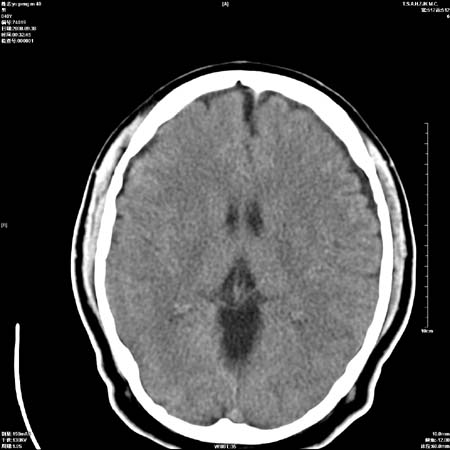

以下是引用zjzjr在2008-10-4 20:29:00的发言:[br]右颞叶皮质区密度略减低,脑沟较对侧变浅,考虑早期脑梗塞,建议mri.左侧小脑幕缘旁可见带状低密度影,轻度占位效应,支持蛛网膜囊肿,枕大池区亦考虑蛛网膜囊肿.

以下是引用流浪星在2008-10-4 20:06:00的发言:[br]大脑大静脉池增宽,脑萎缩引起,目前的ct表现不能解释临床症状,建议短期复查或做mr检查。